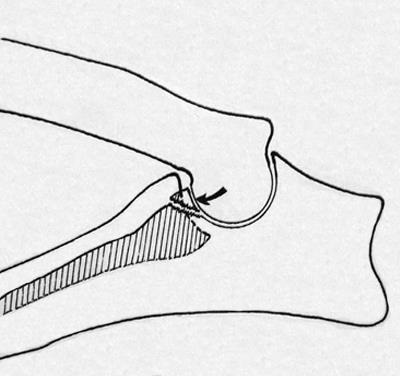

A fragmentáció koronoid az eredménye kialakulhatna egy „lépés” az a hely, az alkar csontjai ízületek miatt lag a fejlesztés a sugár. A másik oka a kár a koronoid társított forgása a radiális csont, akkor fordul elő, amikor az egyén anatómiai jellemzői ín-izomrendszer bicepsz. folyamat túlterhelés is előfordulhat, ha egy kóros formája a cavitas glenoidalis, amelyben a közös egység kissé eltolódik normál helyzetébe, és hozzon létre nyomást a csontra.

Okai szigetelés hooklike folyamat hasonló az oka a töredezettség koronoid fent leírt: a formáció a „lépés” az a hely, az artikuláció, az alkar csontjai, de ez annak köszönhető, hogy a lemaradás a növekedés hosszabb ulna - eredményeként a közös egység felfelé mozog, torlódást okozó hooklike folyamat . Szétválasztása a folyamat továbbra is bekövetkezhetnek késleltetett csontképződés metafízisen közte és a könyök nyúlvány halom - kis terhelés a sérült rész kinövést.